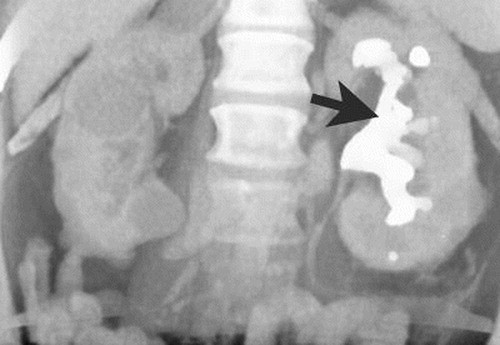

XGP with staghorn calc